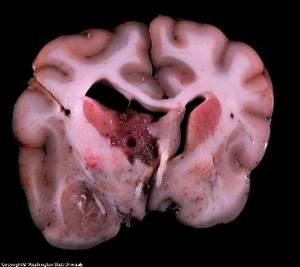

Опухоли головного мозга могут быть классифицированы как «основные» или «вторичные».

Первичные опухоли головного мозга образуются из клеток мозга и клеток мозговых оболочек.

Вторичные опухоли головного мозга – это либо метастазы, которые распространились к мозгу от первичной опухоли вне нервной системы, либо опухоли, которые поражают мозг, вторгаясь или распространяясь на мозговую ткань от смежных тканей, не принадлежащих нервной системе (таких как кости).